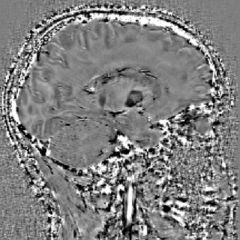

Les traumatismes crâniens regroupent des atteintes neurologiques variées pouvant résulter d’un choc direct, de forces d’accélération‑décélération, d’hémorragies intracrâniennes ou de lésions axonales diffuses. Ces altérations peuvent entraîner un déclin cognitif, des troubles fonctionnels et, dans certains cas, des évolutions neurodégénératives tardives.

Le diagnostic repose sur l’évaluation clinique, l’évolution des fonctions cognitives et l’imagerie, en particulier la tomodensitométrie ou l’IRM. Les symptômes peuvent progresser par paliers selon l’apparition de lésions secondaires, comme les microsaignements.

BIaaS (Brain‑Iron‑As‑A‑Service), grâce à sa capacité à détecter les veines, hémorragies et les microsaignements, pourrait fournir une information objective plus précise sur la nature et l’étendue des lésions post‑traumatiques.